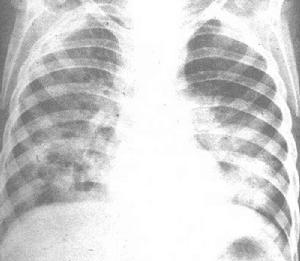

3、胸片:呈支氣管肺炎形態者比大葉性肺炎更多見,病灶多呈斑片狀、網狀、條索狀陰影。應注意的是老年人常因病情嚴重或意識障礙,難以攝出滿意的吸氣相胸片,從而影響病灶的顯示,另外,又因肺組織彈性差、支氣管張力低,肺通氣不足,淋巴回流障礙等原因,致使病灶吸收緩慢,多數需4—6周才能完全吸收。